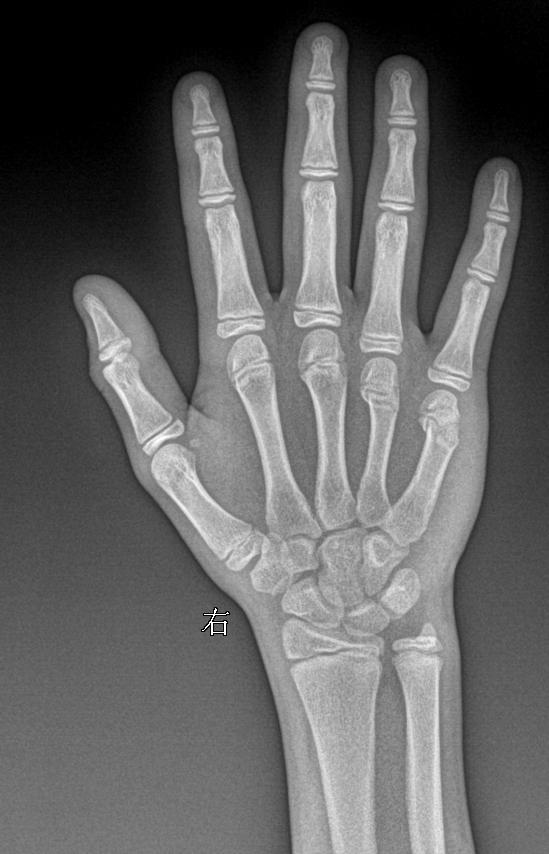

男 13y 外伤 右手正斜位

2025-03-14 16:32